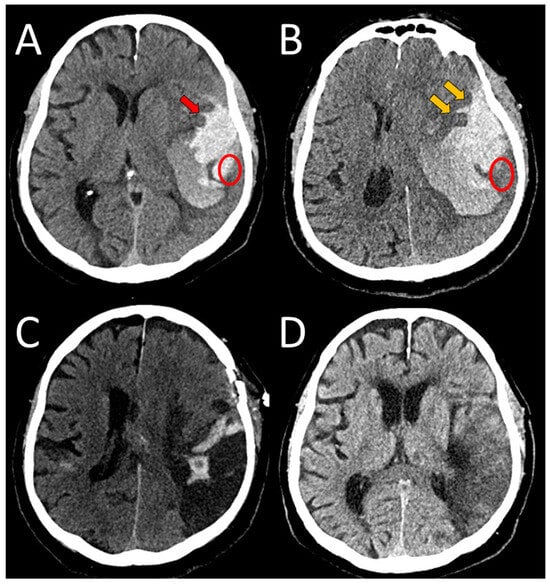

A 77-year-old right-handed male with AH, hyperlipidemia, rheumatoid arthritis, and angina pectoris presented to NED, UMC Ljubljana, in March 2025 with acute-onset confusion and speech impairment. Neurological examination revealed somnolence, global aphasia, right-sided hemianopia, deviation of the eyes and head to the left, right-sided facial paresis, and latent paresis of the right arm (NIHSS 15, mRS 5). An initial head CT revealed ICH in the left parietotemporal lobe, an SDH, and a minor SAH in the left Sylvian fissure (Figure 5A). CT angiography was unremarkable. The patient was admitted for intense monitoring, intravenous hydration, and antihypertensive therapy to the stroke unit. Later that day, he developed worsening of consciousness with vomiting. His left pupil became dilated and poorly reactive and he became comatose (GCS 6). A follow-up CT scan revealed ICH expansion with progressive midline shift (Figure 5B). Therefore, urgent surgical intervention with ICH evacuation was performed (Figure 5C). A cortical biopsy revealed Aβ deposits in the blood vessel walls, in line with CAA (Figure 6). Postoperatively, the patient was admitted to the ICU. According to the improvement revealed in the follow-up CT scans (Figure 5D,E), the sedation was discontinued and he was extubated. During ICU stay, he was treated with antibiotics due to pneumonia and urinary tract infection. On day 25, the patient was transferred to the general ward with global aphasia and right-sided hemiplegia. Due to impaired swallowing, a percutaneous endoscopic gastrostomy was performed. During his hospital stay, he developed another urinary tract infection and pneumonia caused by the same organisms previously identified. Neurological improvement was noted, particularly in motor function. At discharge, he exhibited moderate hemiparesis and right-sided hemianopia; however, his speech production and comprehension remained severely impaired (NIHSS 12). He was able to sit unassisted and take a few steps with support (mRS 5). The patient was discharged to outpatient rehabilitation on day 70.

Figure 5. An axial view of a spontaneous ICH in the left parietotemporal region, measuring 4.5 × 7 × 5 cm, with slight brain shift and edema (A). A small SAH in the upper part of the Sylvian fissure can be seen (red arrow). The follow-up CT scan after clinical worsening showing a significant ICH progression (B), with a more pronounced brain edema and a resultant shift, with further extension of SAH (orange arrows). After a neurosurgical evacuation, a small residual bleeding had been left. The edema and brain shift diminished (C). Gradual resorption of the bleeding and improvement of brain edema during the following weeks (D) is shown. The ellipse denotes the area of surgical biopsy.